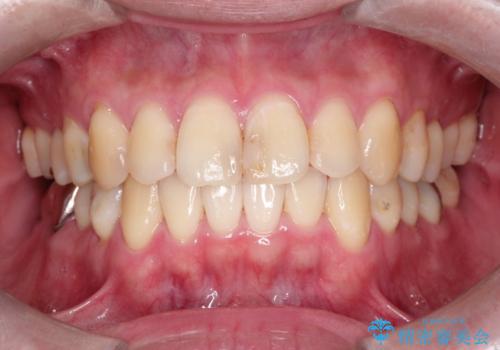

30代女性 前歯のがたつき